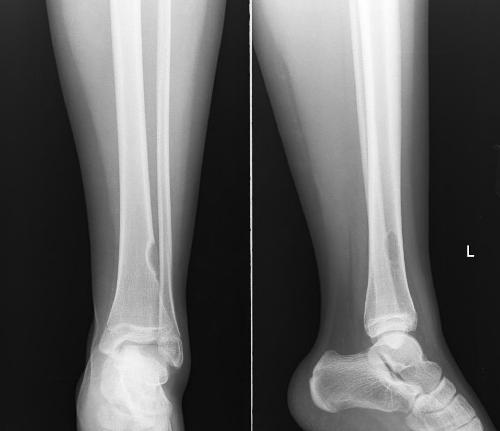

因為骨癌多發生在青少年身上,而這部分人群又比較好動,再加上骨癌早期癥狀并不明顯,很多患者也因此失去了的治療機會,那么骨癌的臨床表現有哪些呢?首先最為明顯的癥狀就是出現關節疼痛,并且晚上疼痛的程...